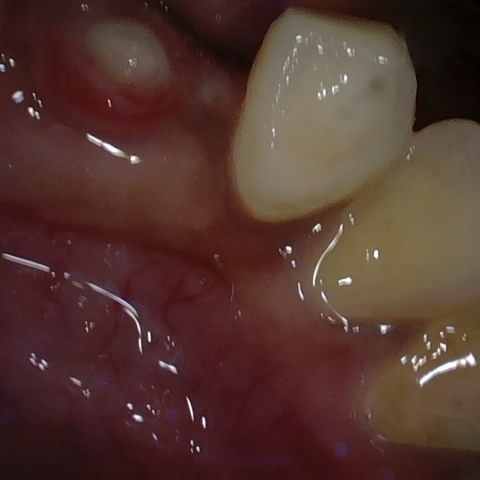

Annotated as "Good"